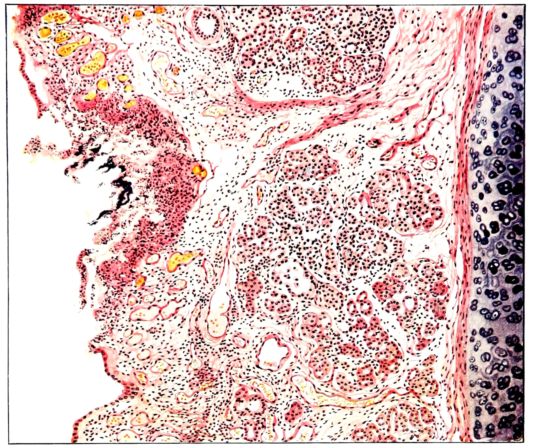

FIG. IV. AUTOPSY NO. 205. CONGESTION AND EDEMA OF THE SUBMUCOSA AND REGENERATION OF THE TRACHEAL EPITHELIUM.

The changes are less marked, perhaps, in the trachea than in its finer ramifications. The mucosa is constantly more or less destroyed and large areas, usually focal, are entirely devoid of their epithelial covering. This is replaced by a sparse exudate, composed largely of red blood cells, mucus, a small amount of fibrin, and nuclear fragments (Fig. II). It may dip into the submucosa for a short distance, but usually these indentures are associated with the ducts of the mucous glands into which the inflammatory reaction extends. A more striking feature than the exudate, however, is the edema and the congestion of the submucosa. The loose areolar tissue of the submucosa is spread widely apart, and throughout it distended blood vessels are very conspicuous. Occasionally such a vessel is broken and actual hemorrhage appears in the submucosa. Occasionally, too, the inflammation extends down the duct to the mucous gland itself, and here, also, aplastic inflammatory reaction is evident, inasmuch as the acini now stain intensely red with the cells undifferentiated from each other and specked here and there by broken remains of the dead nuclei (Fig. III). After the disease has continued for a short period, even at the end of five or six days, some regeneration of the epithelial lining may be seen (3) (Fig. IV). But despite this, the acute picture persists, and there goes on, side by side, an attempted repair characterized by epithelial regeneration and the same evidence of acute change. Since the lesion is essentially a superficial one, scars or contractures of any extent are not encountered in the trachea, even in examples of the disease that have ended fatally only after many weeks.[4]